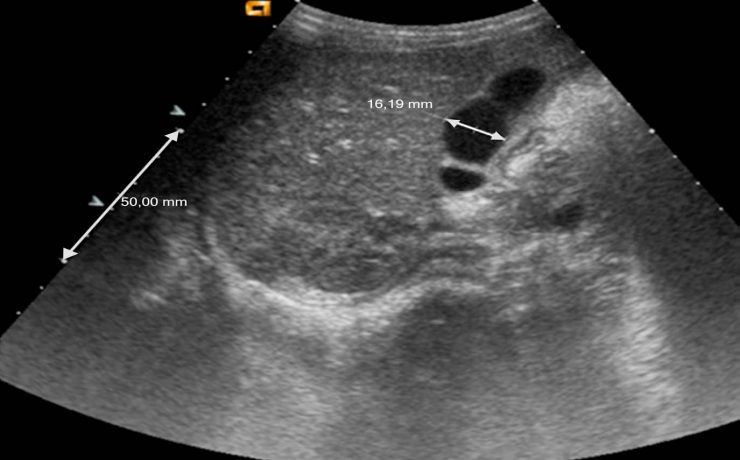

Terapia con células madre en cirrosis

La cirrosis es un proceso difuso caracterizado por fibrosis y conversión de la estructura normal del hígado el nódulos estructuralmente anormales. Este artículo es una revisión de la literatura sobre células madre como terapia para cirrosis hepática. Se establece el transplante de táctico como único tratamiento curativo de Cirrosis. Tiene